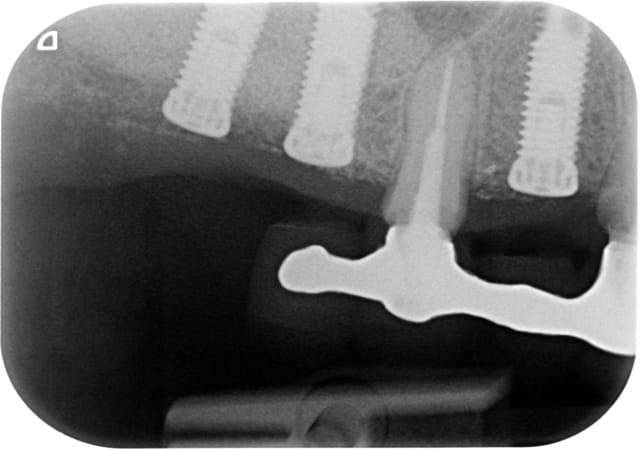

A 10 mars 2008 hjqdhq - Eugenol

B 22 mai 2009 fhhmrm - Eugenol

C 04 juin 2009 vjcx5r - Eugenol

D 15 juin 2009 od7vwg - Eugenol

E 25 juin 2009 hht4ji - Eugenol

F 18 novembre 2009 hhywkg - Eugenol